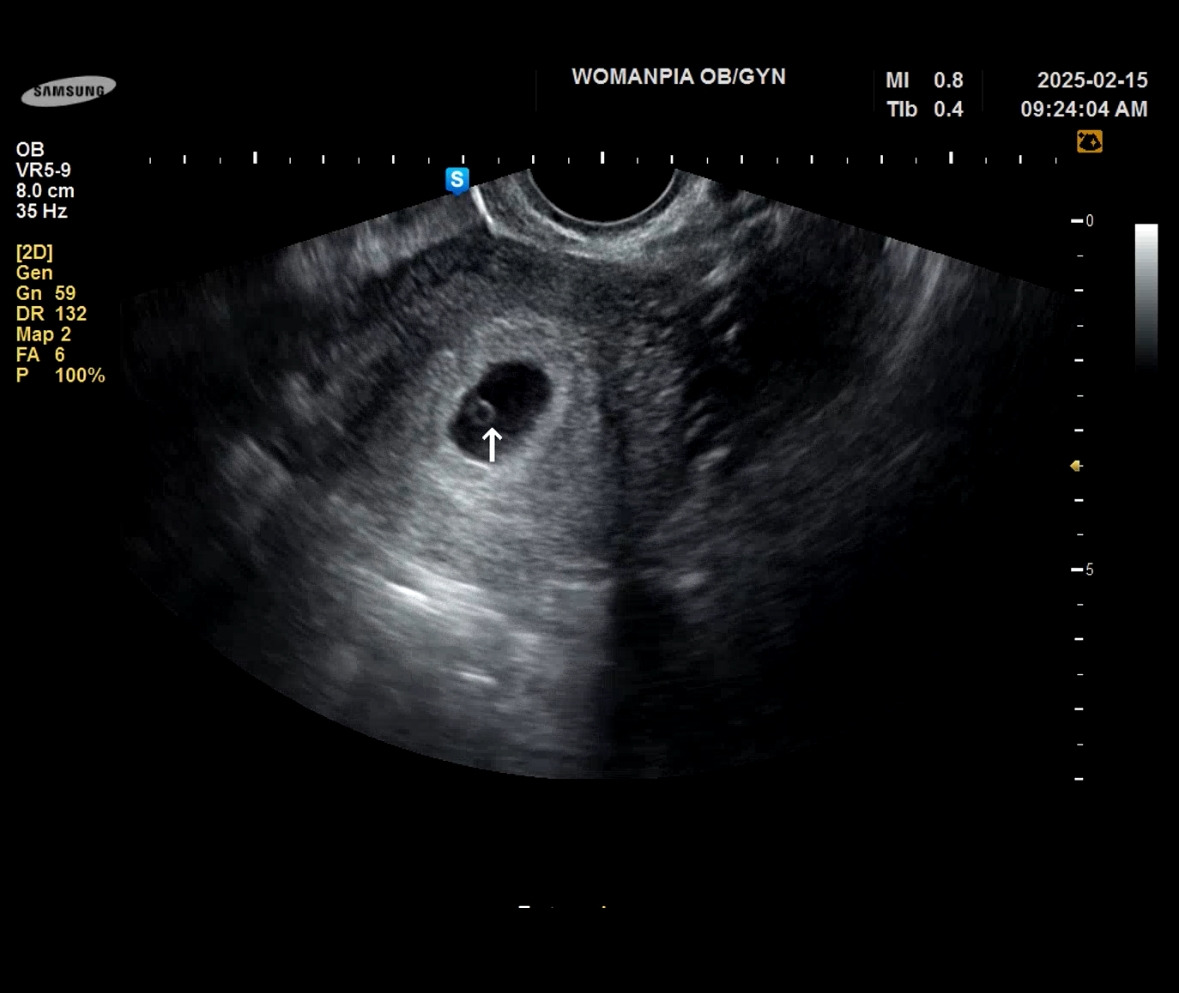

병원을 비교해보고 싶기도 하고 해서 집에서 더 가까운 산부인과로 그다음 주에 방문했다. 난황 말고 아기가 된 모습을 기대하며.. 6주 차 5일에 만난 꼬물이!

머리부터 꼬리까지의 길이가 0.77cm로 6주 차 5 일이라고 이날 확정되었다. 그래서 출산 예정일은 25년 10월 15일! 아직은 출산의 무서움보다는 그날이 너무너무 기다려진다.

머리 쪽에 투명 공간에는 앞으로 뇌가 만들어지는 부분이고 아래에 꼬리는 점점 사라질 거라고 했다. 그리고 머리에 붙어있는 동그라미가 작아지고 있는 난황이다.

지금은 자궁이 꼬물이에 비해 넉넉해 보였다.

심장소리를 잡고 엄청 볼륨을 높여 주셔서 순간 울컥하는 마음에 눈물이 고였다. 신기하다. 1센티가 안 되는 저 꼬물이가 심장이 뛰고 있다는 게.